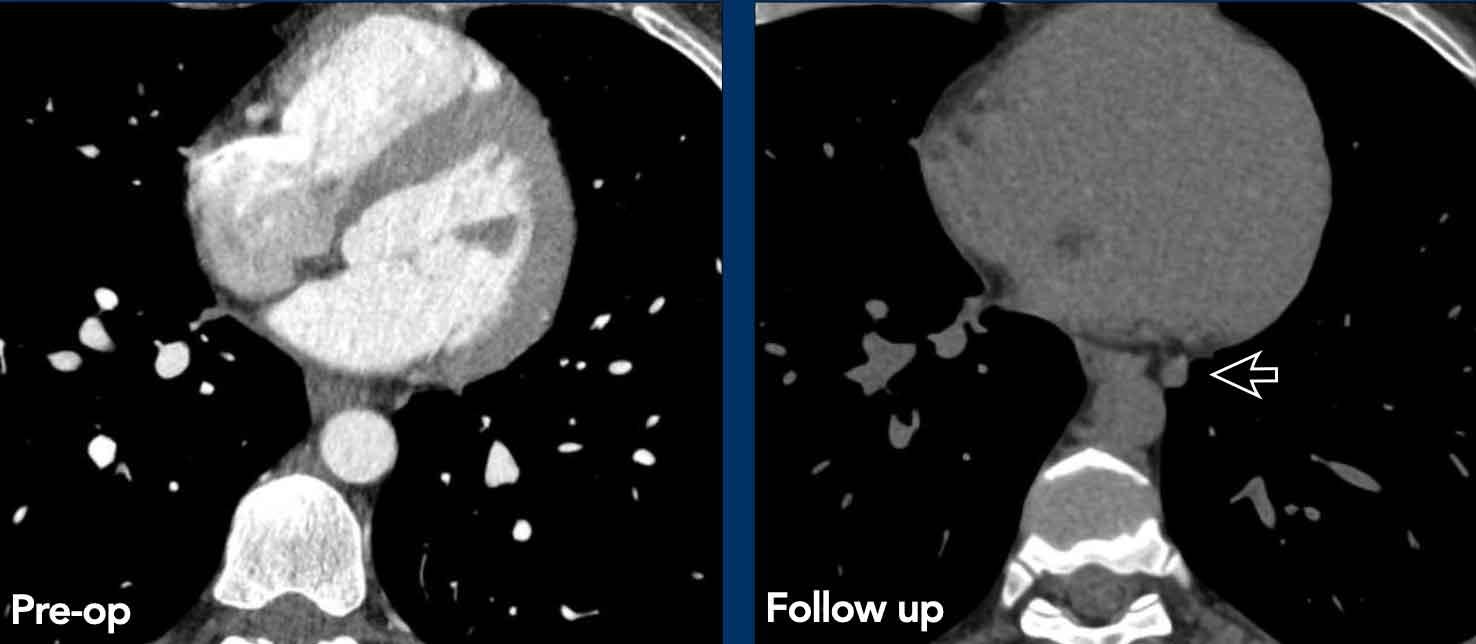

Ca lâm sàng 2

Các hình ảnh này của một bệnh nhân đã được phẫu thuật cắt bỏ thymoma.

Trên phim chụp theo dõi bên trái, phát hiện một tổn thương di căn màng phổi.

Lưu ý rằng nhìn lại, đã có một tổn thương màng phổi rất nhỏ trên phim chụp trước phẫu thuật.

Bài học rút ra là khi nghĩ đến thymoma, cần phải khảo sát màng phổi một cách hết sức tỉ mỉ.

“Bạn chỉ tìm thấy những gì bạn đang tìm kiếm”.